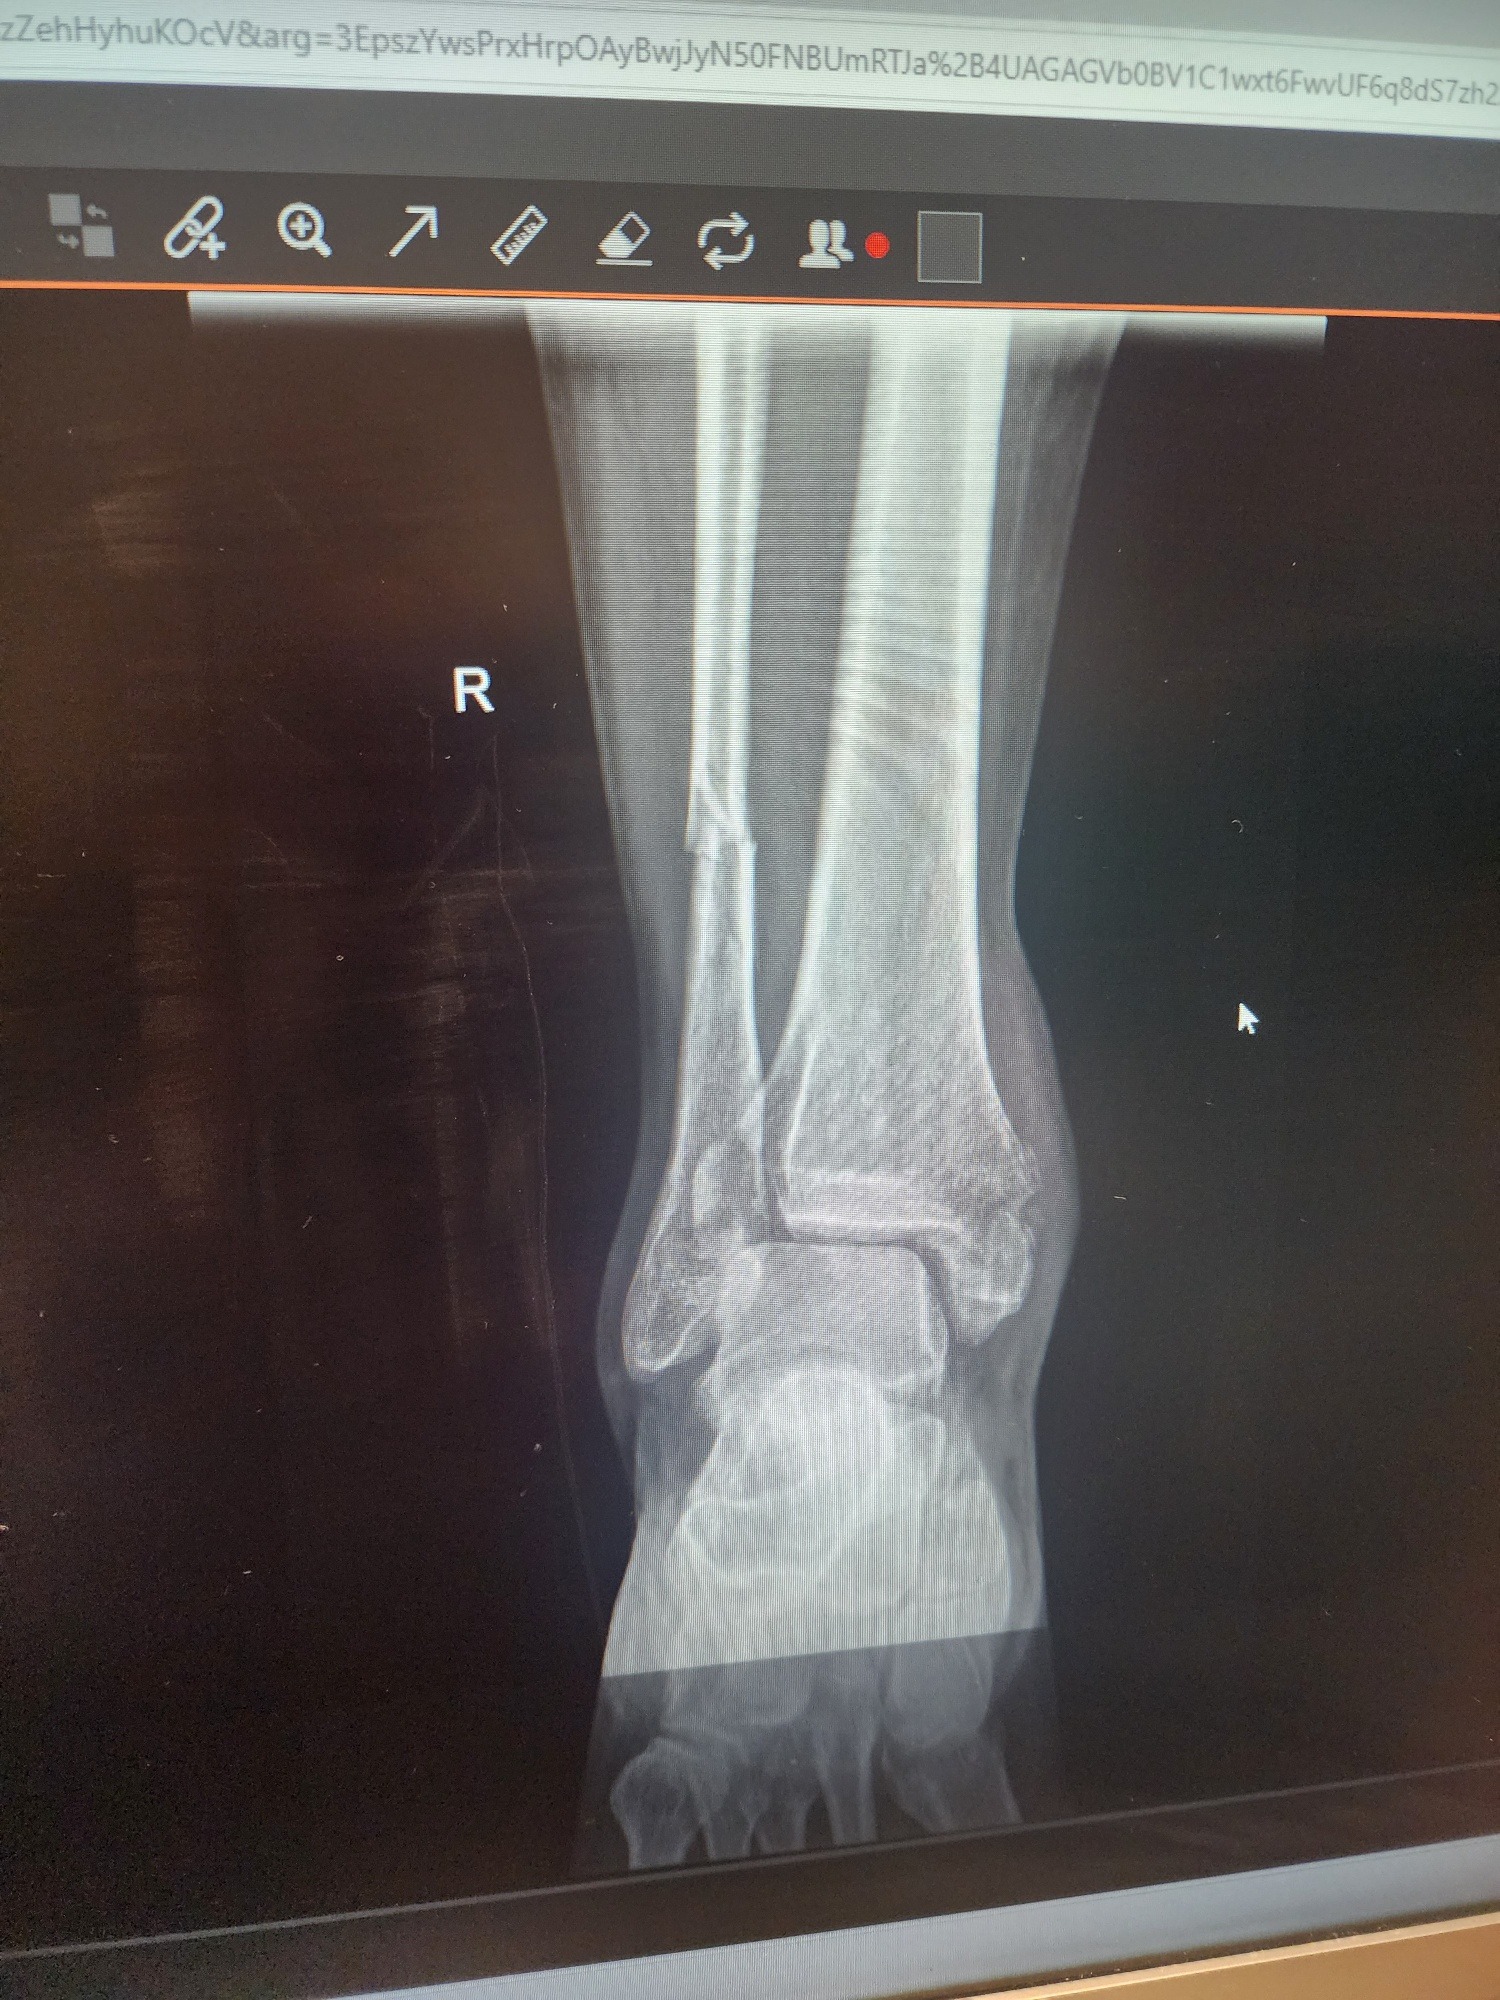

I’m reaching out during a really challenging time. I recently suffered a fractured ankle that requires orthopedic surgery. While I’m fortunate to have insurance, the out-of-pocket expenses for the surgery, follow-up care, and recovery are still significant.